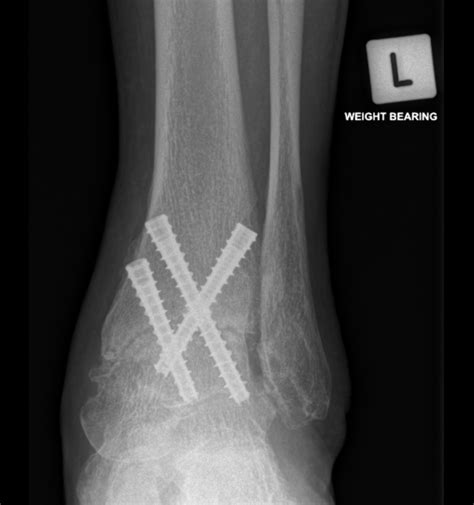

• Fixation: The bones are aligned and held in place using screws, plates, or rods. These fixation devices provide stability while the bones heal and fuse together.